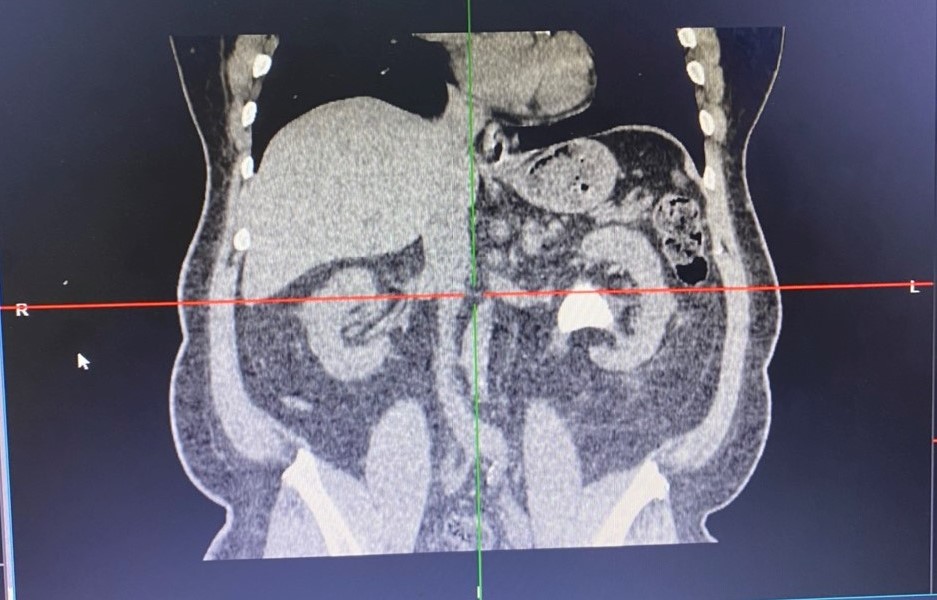

Bệnh nhân nam 48 tuổi biết mình có sỏi thận mấy năm nay nhưng không theo dõi hay điều trị. Chỉ đến khi bị xuất huyết tiêu hóa mới vào viện thăm khám và bác sĩ Bệnh viện đa khoa Quốc tế Hải Phòng phát hiện viên sỏi của bệnh nhân với kích thước 4cm đã bắt đầu gây biến chứng làm giãn thận và suy thận. Tình huống này, nếu không được can thiệp kịp thời dễ dẫn đến nguy cơ nhiễm trùng, suy thận, ảnh hưởng đến tính mạng của người bệnh.

Xác định rõ tình trạng bệnh của bệnh nhân kết hợp người bệnh có thể trạng béo phì (nặng 120kg) cùng nhiều bệnh lý phối hợp như đái tháo đường, viêm loét đường tiêu hóa, rối loạn lipid máu, nguy cơ tắc mạch… bác sĩ Khoa Ngoại thận tiết niệu – Nam học đã phải tiến hành hội chẩn, đánh giá rất kĩ lưỡng và cân nhắc lựa chọn phương pháp điều trị tối ưu nhất cho bệnh nhân là sau khi điều trị ổn định tình trạng xuất huyết tiêu hóa, sẽ tiến hành tán sỏi qua da bằng đường hầm nhỏ. Quá trình phẫu thuật gặp nhiều khó khăn về gây mê, gây tê do bệnh nhân béo phì, cổ ngắn, khó đặt tư thế và tìm đường vào thận song ekip phẫu thuật đã khéo léo tạo đường hầm qua da, sử dụng năng lượng laser phá vỡ sỏi thành mảnh nhỏ để lấy ra ngoài. Kết quả, đã xử lý hết sỏi sau một lần tán, phẫu thuật đảm bảo an toàn, hiệu quả. Đến nay, người bệnh đã hồi phục và xuất viện.